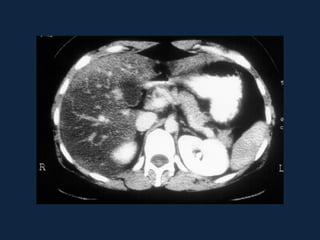

SÍNDROME DE BUDD-CHIARI

• Obstrução da drenagem venosa

hepática no plano das veias

hepáticas ou da VCI.

• Associada às síndromes

mieloproliferativas, trauma, HPN,

carcinoma hepatocelular, gravidez e

uso de anticoncepcionais.

• Ascite, hipertrofia do lobo caudado,

hipertensão portal, aspecto “em

mosaico” do parênquima hepático.

Distribuição perivascular

• Budd-Chiari

– Aumento do lobo

caudado

– Atrofia do restante do

parênquima

• “Compressão

periférica”

– Nódulos regenerativos

•  T1

• ,  ou  T2